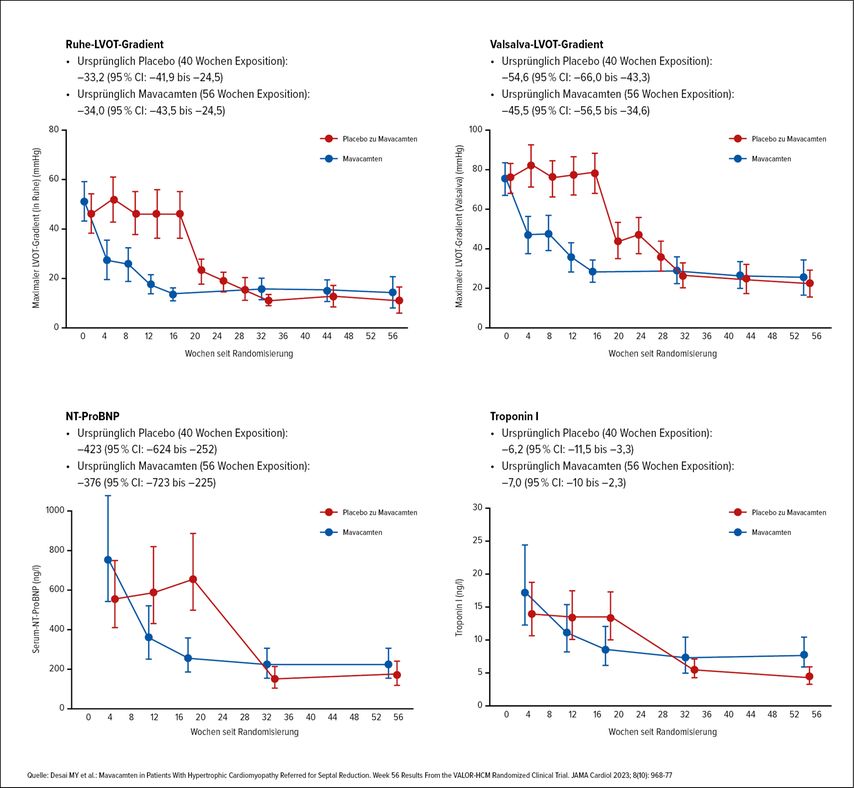

Mavacamten wurde auf Basis der Phase-III-Studie EXPLORER-HCM, in der die Verbesserung der maximalen Sauerstoffaufnahme und der NYHA-Klasse gezeigt wurde, als erster Myosininhibitor zugelassen. Mavacamten verbesserte in EXPLORER-HCM auch radiografische Endpunkte und die Lebensqualität.4 Dass es unter Mavacamten auch zu günstigen strukturellen Veränderungen am Herzen, wie z.B. einer Abnahme der Wanddicke, kommt, wurde in der Studie VALOR-HCM demonstriert. VALOR-HCM untersuchte, ob sich Patient:innen, bei denen eine chirurgische oder interventionelle Behandlung ihrer HCM indiziert wäre, unter Therapie mit Mavacamten so weit verbessern, dass der Eingriff nicht mehr indiziert ist. Tatsächlich waren nach 16 Behandlungswochen nur noch 18% der Patient:innen in der Mavacamten-Gruppe noch Kandidaten für eine Ablation bzw. entschieden sich für eine solche. Unter Mavacamten konnten schließlich 44% der Patient:innen um mindestens zwei NYHA-Klassen besser eingestuft werden. Auch das linksatriale Volumen und der myokardiale Strain (als Maß für die globale und regionale Kontraktilität des Herzmuskels) verbesserten sich.5

Im Langzeit-Follow-up nach 128 Wochen erfüllten schließlich nur 15,7% der gesamten Studienpopulation (initial auf Mavacamten eingestellte sowie ab Woche 16 von Placebo auf Mavacamten umgestellte Patient:innen) die Kriterien für eine Septumreduktionstherapie oder entschieden sich dafür.6 Mittlerweile sind aus den Studien EXPLORER-HCM und VALOR-HCM Daten über bis zu 180 Wochen publiziert, die anhaltende Reduktionen des LVOT-Gradienten und des NT-proBNP zeigen.7